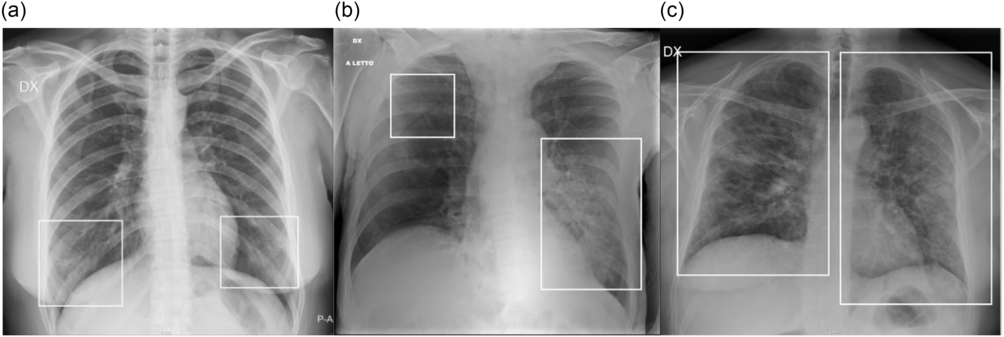

Two radiologists (M.C., a radiologist with 9 y of experience; M.O., a radiologist with 7 y of experience) in consensus assessed for each CXR: (1) the presence of lung abnormalities, described as consolidation, ground-glass opacities (GGO), or nodules, according to the Fleischner Society glossary of termsReference Hansell, Bankier and MacMahon13 (Figure 1); (2) their distribution, classified into (i) “peripheral,” “central,” or “both”; and into (ii) “unilateral” or “bilateral.” The presence of pleural effusion was recorded.

FIGURE 1 Examples of CXR Abnormalities. a: CXR showing a focal GGO involving the middle-upper fields of the right lung (frame). b: CXR showing area of consolidation in the lower right fields (frame). GGO are recognizable in the lower fields of the left lung.

A radiographic severity score, according to Wong et al.,Reference Wong, Lam and Fong14 was independently assigned by 2 radiologists (M.P., radiologist with 7 y of experience; G.O., radiologist with 25 y of experience), depending on the extent of involvement by consolidation or GGO (0 = no involvement; 1 = <25%; 2 = 25-50%; 3 = 50-75%; 4 = >75% involvement), for each lung, with a maximum score of 8 for CXR. Some examples are provided in Figure 2. Interobserver agreement was evaluated.

FIGURE 2 Examples of CXR Severity Score Assignment. a: CXR showing focal bilateral GGO in the lower fields (frames). On both left and right lung, the involvement was < 25%; therefore, the CXR severity score assigned was 1 for each lung, with a global score of 2. b: CXR showing bilateral parenchymal opacities (frames): a huge area of consolidation in the middle-lower left fields with contextual air bronchogram, while a focal area of GGO is recognizable in the upper fields of the left lung; the extension on the left side was > 50% (score 3), whereas the involvement on the right side was < 25% (score 1); therefore, the overall score was 3 + 1 = 4. c: CXR showing bilateral involvement, with mixed areas of GGO and consolidation (frames) involving all the lung fields. On both left and right lung, the involvement was > 75% (score 4); therefore, the global score was 4 + 4 = 8.